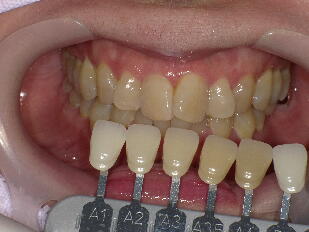

5.歯のホワイトニング ![]() ![]() ![]() ![]() ![]() ![]()

※歯のホワイトニングは期間、結果に大きな個人差があります。また歯の色が元の色に戻

っていく後戻りという現象も生じますので、詳細は歯科医師にご相談ください。